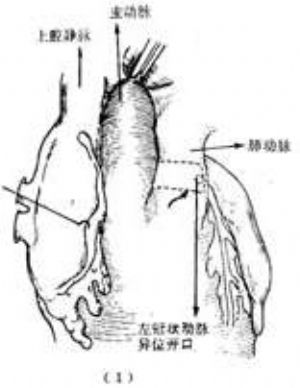

右冠狀動脈異位起源於肺動脈 右冠狀動脈異位起源於肺動脈較之左冠狀動脈遠爲少見,到1979年僅報道17例(LeBerg等),大多數病例不呈現臨牀症狀,在屍體解剖時才明確診斷。由於右心室壁薄,張力低,兩側冠狀動脈之間又可形成側支循環,因此右冠狀動脈分佈區域的心肌氧供仍能維持,嬰兒期不呈現臨牀症狀,生長發育亦無異常,進入成年期後,少數病人可出現心力衰竭或猝死。升主動脈和肺動脈造影檢查,可顯示異位起源的右冠狀動脈,從而明確診斷。

治療方法是在體外循環下施行手術,將右冠狀動脈開口連同其周圍的部分肺動脈壁從肺動脈切下後移位植入升主動脈根部前壁。由於右冠狀動脈較長,且起源於肺動脈前壁靠近升主動脈,移植術操作比較簡易(圖4)。